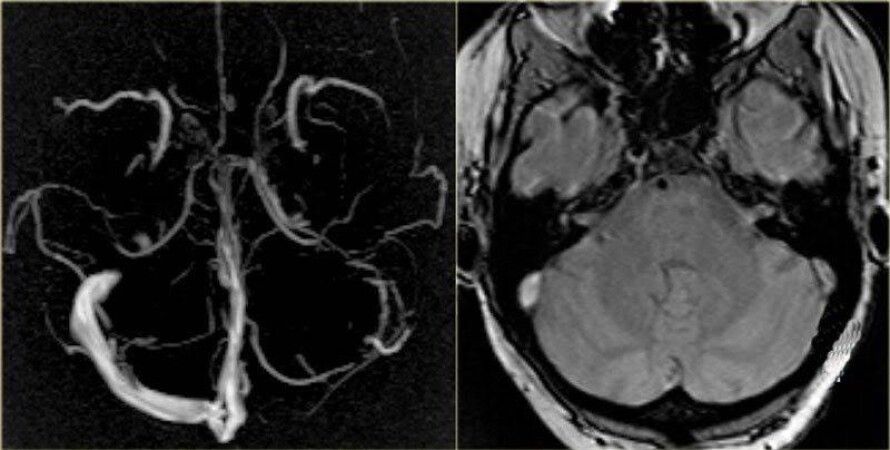

Тромб в мозгу на МРТ | Фото: "Магнит"